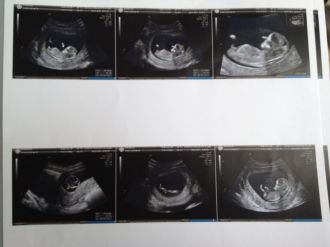

Nouvelle rencontre avec bébé :)ça y'est c'était le jour J, écho des 18sa (enfin 17sa+5)! ravie d'avoir revue notre petite crevette qui a bien grandit d ailleurs :)

BIP : 41mm

Longueur fémorale : 23,3mm

Fréquence cardiaque : 166 Bpm

circonférence abdominale : 119mm

périmètre crânien : 148mm

bref tout a fait dans les courbes ! bébé bougeait énormément durant l'écho et avait le cordon ombilical entre les jambes mais bon on a tout de même une petite prédiction sur le sexe et apparemment ce serait une petite fille, bon a reconfirmer lors de la prochaine écho des 22sa tout de même car pas sure a 100% !! en tout cas si c'est bien une puce ravie car j'aurai comme on dit le choix du roi !!!